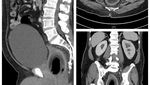

Sebuah hasil rontgen menunjukkan ada sekitar 800 jarum 'susuk' yang bersarang di tubuh seorang wanita. Radiografi perut dari pasien yang sama juga menunjukkan jarum berada paling banyak di area panggul. (Foto: Journal of Radiology Case Reports)